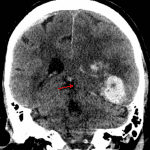

- Large acute parenchymal hematoma centered in the left temporal resection bed measuring 8.5 x 6 x 5.5 cm (volume = 140 mL) with surrounding vasogenic edema

- Associated mass effect with left hemispheric sulcal effacement, left to right midline shift measuring 13 mm at the Foramen of Monro with left subfalcine herniation, near complete effacement of the left lateral ventricle, and left uncal herniation with partial effacement of the suprasellar cistern and mass effect upon the midbrain

- Small amount of hemorrhage extending into the left lateral ventricle

Large acute parenchymal hematoma centered in the left temporal resection bed measuring 8.5 x 6 x 5.5 cm (volume = 140 mL) with surrounding vasogenic edema. Associated mass effect with left hemispheric sulcal effacement, left to right midline shift measuring 13 mm at the Foramen of Monro with left subfalcine herniation, near complete effacement of the left lateral ventricle, and left uncal herniation with partial effacement of the suprasellar cistern and mass effect upon the midbrain. No cerebellar tonsillar herniation.

Small amount of intraventricular hemorrhage in the left lateral ventricle. Mild dilation of the posterior body and atrium of the right lateral ventricle raises concern for developing noncommunicating hydrocephalus.